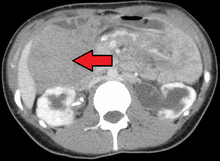

Desmoid tumor as seen on CT scan

Aggressive fibromatosis is a rare condition marked by the presence of desmoid tumors. Desmoid tumors can arise in virtually any part of the body, and are tumors that arise from cells called fibroblasts, which are found throughout the body and provide structural support, protection to the vital organs, and play a critical role in wound healing. These tumors tend to occur in women in their thirties, but can occur in anyone at any age. They can be either relatively slow-growing or malignant. However, aggressive fibromatosis is locally aggressive. When they are aggressive they can cause life-threatening problems or even death when they compress vital organs such as intestines, kidney, lungs, blood vessels, nerves etc. Most cases are sporadic, but some are associated with familial adenomatous polyposis (FAP). Approximately 10% of individuals with Gardner's syndrome, a type of FAP with extracolonic features, have desmoid tumors.[1]

Desmoid tumors may be classified as extra-abdominal, abdominal wall, or intra-abdominal (the last is more common in patients with FAP). It is thought that the lesions may develop in relation to estrogen levels or trauma/operations.